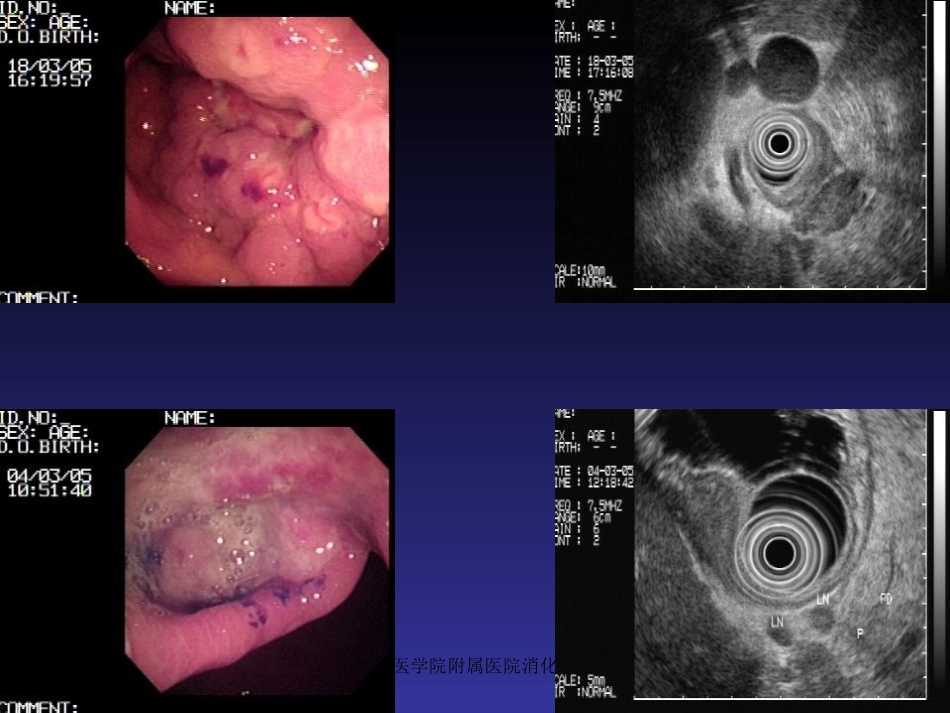

海南医学院附属医院消化内科•概述•胃、十二指肠出血分为:a)静脉曲张性出血b)非静脉曲张性出血消化性溃疡胃、十二指肠粘膜糜烂•非静脉曲肿瘤张性出血Dieculafoy氏溃疡血管畸形海南医学院附属医院消化内科海南医学院附属医院消化内科海南医学院附属医院消化内科海南医学院附属医院消化内科一.胃、十二指肠出血治疗方法•药物治疗•外科手术治疗•X线介入血管栓塞治疗•内镜下治疗内镜治疗优势:能够直观观察到胃、十二指肠出血部位,并能采取各种止血方法作相应止血治疗,从而避免以往常规外科手术治疗方法。海南医学院附属医院消化内科二、适应症与禁忌症适应症:•消化性溃疡并出血•Dieculafoy氏溃疡出血•急性胃粘膜病变并出血•血管畸形并出血•肿瘤并出血•Mallory-Weiss综合征•其他原因所致胃、十二指肠血管出血海南医学院附属医院消化内科禁忌症•胃镜检查禁忌者•失血性休克尚未纠正•安装心脏起搏器者禁忌高频电凝切除海南医学院附属医院消化内科三、术前准备•胃镜检查一般在出血4~48小时内进行。•如有休克,先抗休克治疗,待血压稳定后再胃镜检查和治疗。•如活动性出血可边输血、输液纠正休克,边准备急诊内镜治疗。•有严重并存疾病及老年患者等高危人群,经积极处理但血流动力学状态不稳定者,需考虑急诊内镜止血治疗。海南医学院附属医院消化内科•内镜治疗前应向病人家属做好解释工作,取得病人的配合,并履行知情同意书上签字手续。•在内镜操作过程中监测血压、心率、血氧饱和度。•术中可酌情静脉注射安定和654-2各10mg,并保持静脉通道开放。•以防止误吸发生,事前做好气管插管的准备工作。•对有高危人群或有心血管系统疾病者检查及治疗中均心电监护。海南医学院附属医院消化内科四、止血操作方法1、钛夹止血其原理:在内镜直视下对出血血管钳夹或周围组织夹闭缝合,利用其闭合产生机械性压迫达到止血目的。器械准备:a)电子胃镜b)钛夹Olympus的Clip-850c)钛夹置放器(投放器)海南医学院附属医院消化内科海南医学院附属医院消化内科海南医学院附属医院消化内科•操作方法及步骤•1)洗胃:如胃内出血部位血液或血凝块影响出血病灶视野,应插胃管用生理盐水洗尽胃内积血。•2)胃镜检查:寻找出血部位、病变范围、病变性质及有无活动性出血。•3)钛夹止血:将钛夹安装于投放器上,经内镜活检钳道插入,找到出血血管或部位后,助手后拉投放器外管,露出钛夹,再后拉手柄,使钛夹张开到最大程度,并可根据需要旋转钛夹方向,钛夹对准出血血管或组织后,助手用力后拉投放器手柄,使钛夹夹闭后再前推手柄,使两者脱离。多少取决于出血情况。海南医学院附属医院消化内科海南医学院附属医院消化内科海南医学院附属医院消化内科海南医学院附属医院消化内科•注意事项•1)溃疡并出血者应避免钳夹坏死组织。•2)选择钛夹金属片前端的角度应大于90度。•3)尽可能将显露血管与周围组织一起钳夹,以达到最理想的止血效果。海南医学院附属医院消化内科2、氩离子凝固治疗•原理:氩离子血浆凝固术(APC)是利用高频输出电极使流向电极末端2~10mm处的氩气离子化,氩离子可以导电,将氩离子束传送至靶器官,能使组织表面凝固,从而起到止血和破坏有关组织等治疗作用。海南医学院附属医院消化内科•器械准备•前视胃镜•氩离子发生器(APC300)•高频电发生器(EndoCutICC200)•APC探头(直径2.3mm长2.2mm)海南医学院附属医院消化内科电凝止血原理海南医学院附属医院消化内科电凝止血示意图海南医学院附属医院消化内科•操作方法与步骤•开氩离子器瓶的阀门,注满氩气,气流量为2L/分,APC功率设为50~60W。•胃镜下找到出血病灶后,将APC探头由活检钳钳道插入。•APC探头置于距出血部位2~3mm以内进行凝固治疗,直至组织发白凝固,出血停止。•胃镜下观察数分钟,确认渗血停止后退镜。海南医学院附属医院消化内科氩离子电凝止血海南医学院附属医院消化内科海南医学院附属医院消化内科3、微波凝固术•原理:内镜下微波凝固治疗是一种新技术,它是通过微波产生热效应使局部组织坏死及小血管痉挛、血管壁肿胀、内皮细胞破坏等导致血管内血栓形成,达到止血目的。...